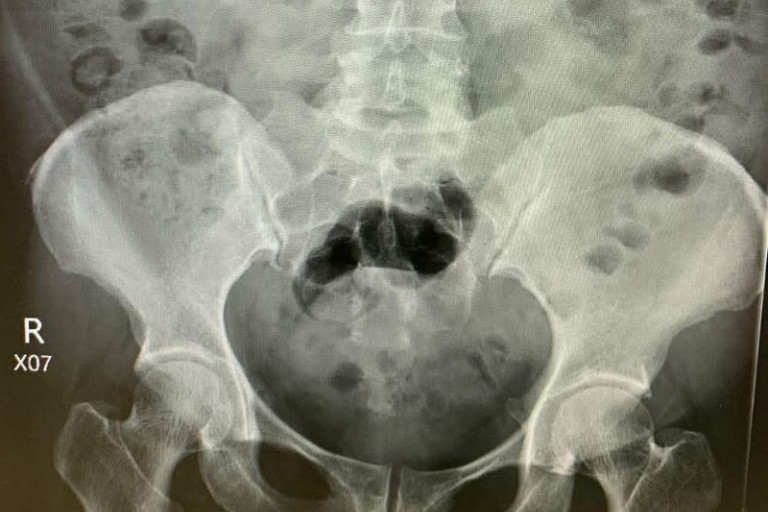

วันนี้ผมต้องผ่าตัดนิ่วเขากวางขนาดใหญ่ แต่ปัญหาคือเครื่องมือที่ใช้สลายนิ่วเป็นประจำเสีย ซ่อมไม่ได้ซะด้วยต้องซื้อใหม่สถานเดียว จะใช้เครื่องมือกระแทกนิ่วตัวอื่นก็หวั่นๆ

สุดท้ายแก้ปัญหาด้วยการยืมเครื่องมือสลายนิ่วมาใช้ 2 สัปดาห์ สอบถามผู้แทนเครื่องมือถึงราคา สนนราคา 2 ล้านกว่าบาท โรงพยาบาลก็ไม่ค่อยมีเงินจึงไม่รู้ว่าเมื่อไหร่จะมีใช้